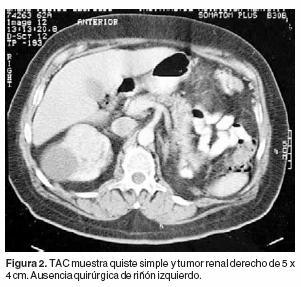

Carcinoma de células claras Carcinoma endometrioide Tumores Neuroendócrinos Carcinoma de pequenas células Carcinoma de grandes células Tumor neuroendocrine bem diferenciado Paraganglioma VIII3 Estadiamento O fator prognóstico mais importante para o carcinoma da pelve renal/ureter é o estadiamento e a profundidade da invasão. REVISIÓN Guía del carcinoma de células renales* Renal cell carcinoma guideline Börje Ljungberg a, Damian C Hanbury b, Marcus A Kuczyk c, Axel S Merseburger c, Peter FA Mulders d, JeanJacques Patard e, Ioanel C Sinescu f a Servicio de Cirugía y Ciencias Perioperatorias, Urología y Andrología, Universidad de Umea, Umea, Suecia b Servicio de Urología, Hospital de Lister, Mill. Caso clínico Se presenta el caso de un paciente de 78 años de edad al que se descubren dos neoplasias epiteliales independientes y sincrónicas en el mismo riñón El tumor dominante, el que llevó al paciente al médico y por el cual se realizó la nefrectomía corresponde a un carcinoma de células claras típico.